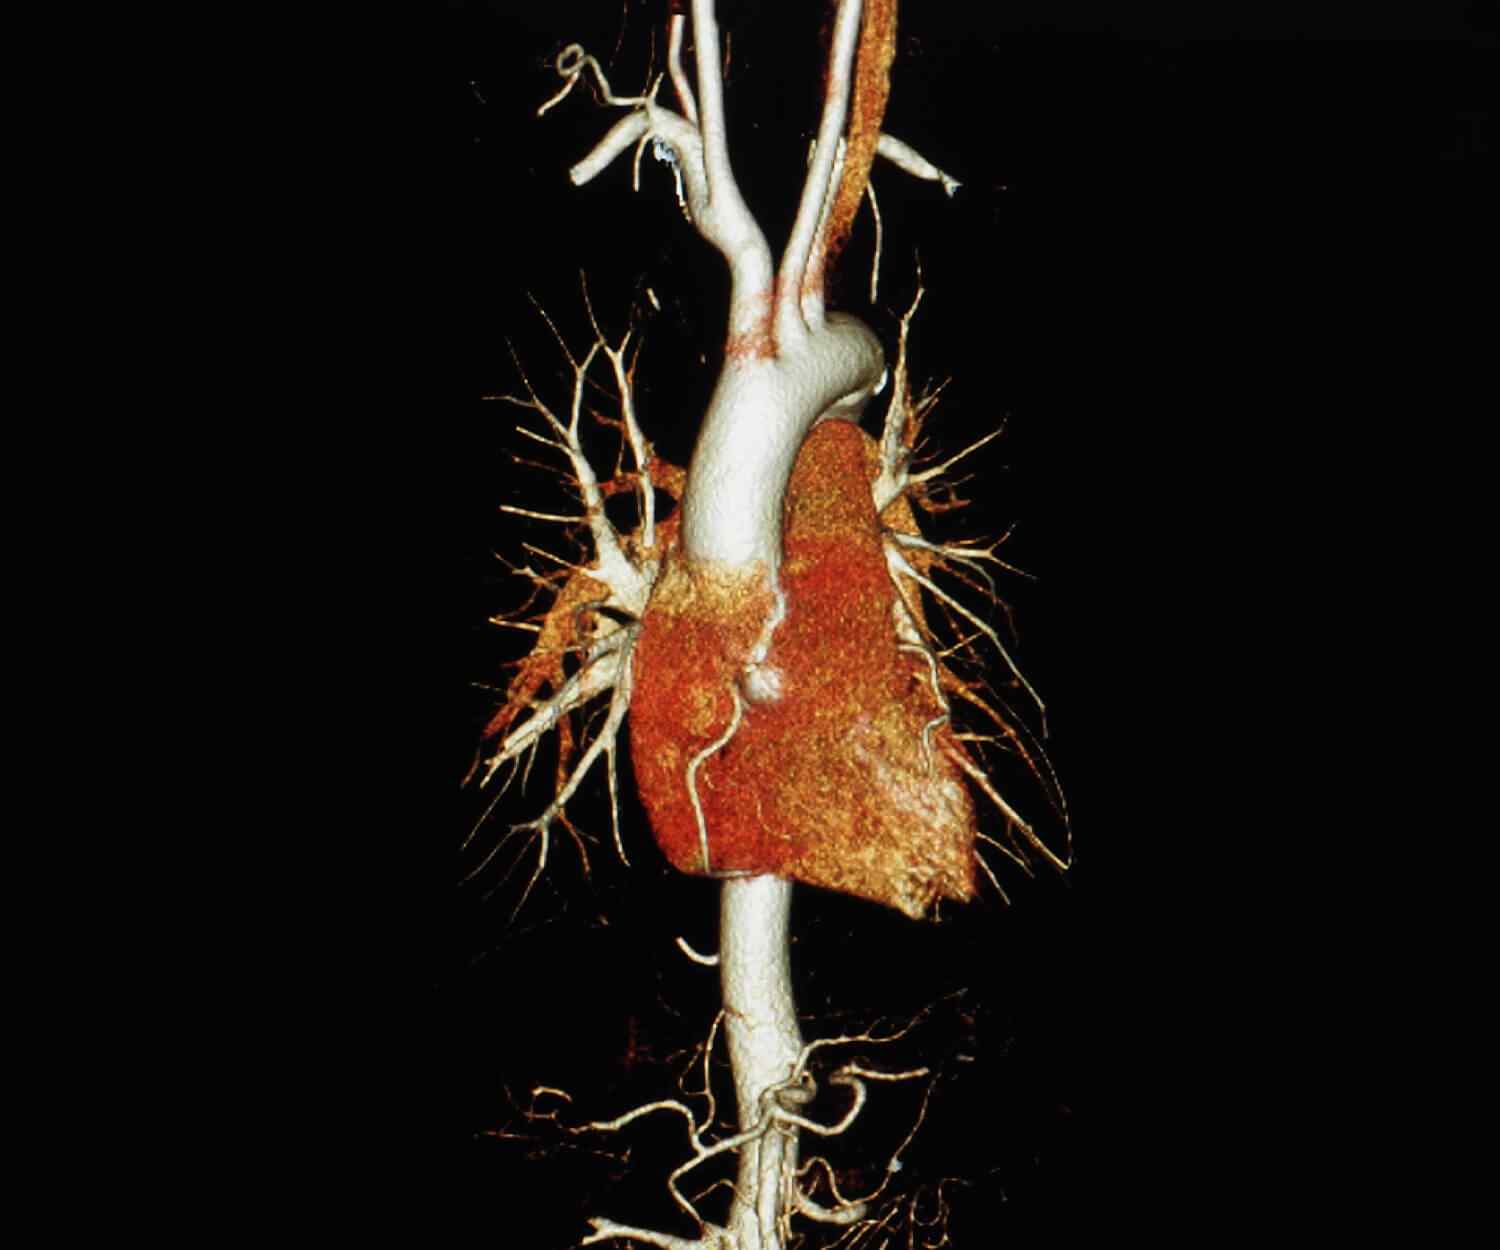

If you have known coronary artery disease, your doctor might recommend the traditional approach because you can also receive treatment during the procedure. Your doctor should give you instructions about how to prepare for CT.